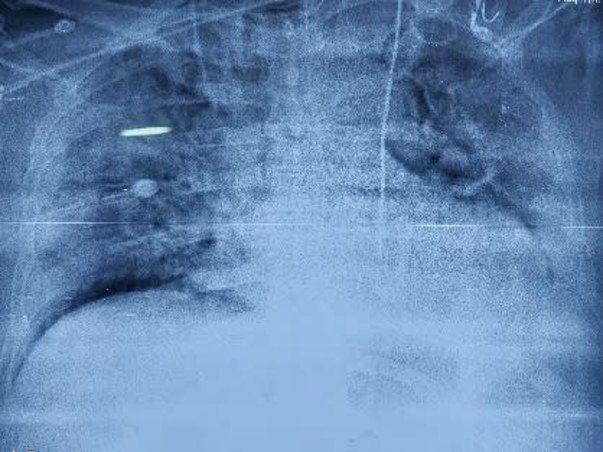

Our papa is suffering from Lungs Infection for a few months. He is having fibrosis in his lungs because of which he has been on ventilator support for months now.